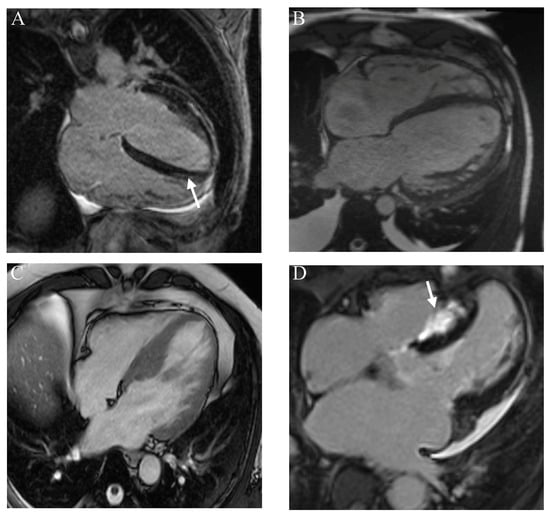

| Cardiac Disorder | Clinical Features | Imaging Features | Biochemical/Genetic Features |

|---|---|---|---|

| HCM |

|

| DCM |

| ACM |

| Amyloidosis |

| Myocarditis |